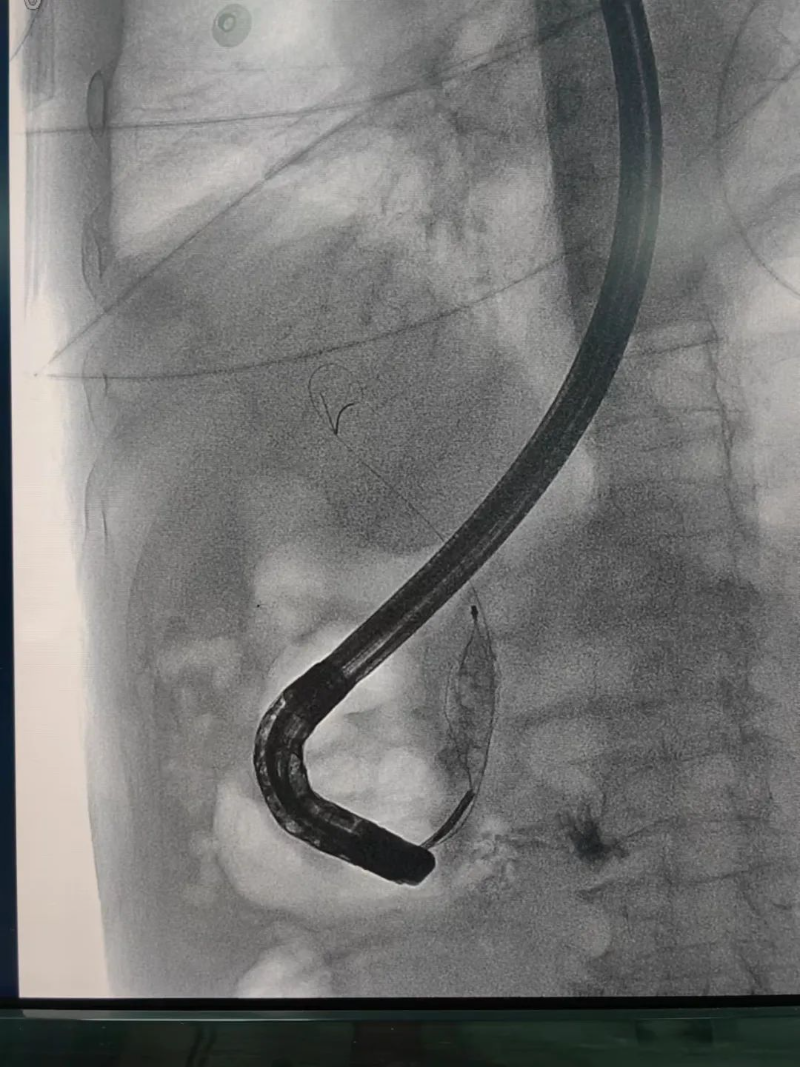

入院后,胡斌立即組織全科進(jìn)行病例討論,制定治療方案。經(jīng)討論,一致同意行ERCP(內(nèi)鏡下逆行胰膽管造影技術(shù))解除膽道梗阻?!班u爺爺年紀(jì)較大,且合并多種疾病,ERCP治療代替開腹手術(shù),創(chuàng)傷小、恢復(fù)快,是最好的選擇。”胡斌介紹道。

在與患者及家屬充分溝通并告知其手術(shù)的必要性及風(fēng)險(xiǎn)后,經(jīng)患者及家屬同意,科室立即與內(nèi)鏡中心、麻醉科、介入室取得聯(lián)系,在各科室的協(xié)助下,普外科胡斌主任醫(yī)師、闕劍鋒副主任醫(yī)師、陳聲飛副主任醫(yī)師共同完成了此次手術(shù),僅用半小時(shí)就將鄒爺爺?shù)哪懣偣芙Y(jié)石取出。

經(jīng)內(nèi)鏡逆行胰膽管造影術(shù)(以下簡(jiǎn)稱ERCP)是治療膽管結(jié)石的首選方法,ERCP屬于介入和微創(chuàng)手術(shù),可以有效減少傳統(tǒng)手術(shù)對(duì)患者身體的創(chuàng)傷,能快速緩解臨床癥狀,降低相應(yīng)并發(fā)癥的發(fā)生,改善肝功能,促進(jìn)患者康復(fù)、減少圍術(shù)期應(yīng)激,縮短住院時(shí)間,是項(xiàng)較安全、直觀、可靠的治療手段,對(duì)肝膽、胰疾病有較高的診斷和治療價(jià)值。

文章配圖

ERCP是經(jīng)口內(nèi)鏡膽道治療技術(shù)。是國(guó)際公認(rèn)的膽管胰腺系統(tǒng)疾病診斷的金標(biāo)準(zhǔn),是確診膽管結(jié)石的最佳方法。在ERCP基礎(chǔ)上,可以同時(shí)進(jìn)行膽總管結(jié)石取石術(shù)、Oddis括約肌切開術(shù)、膽總管支架植入術(shù)、鼻膽汁引流術(shù)等微創(chuàng)手術(shù),對(duì)膽總管結(jié)石等疾病進(jìn)行安全、快速、有效的治療。